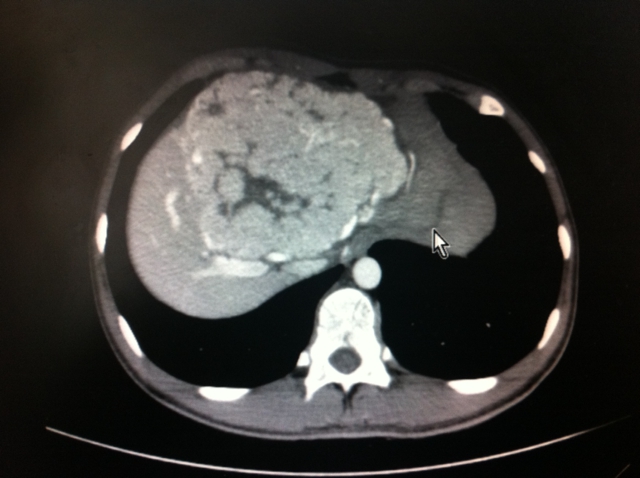

术前由普外一科专家刘浔阳、黄飞舟、聂晚频等教授共同会诊,进行了深入的术前讨论,制定了详细的手术方案。主管医师张瑞主治医师进行了细致的术前准备。手术由黄飞舟、罗宏武两位教授共同主刀,历时3小时,成功为小雨将巨大肝脏肿块和肝左三叶完整切除(图2)。小雨术后恢复顺利,术后仅8天便康复出院。出院时,小雨的母亲感激地说:“感谢湘雅三医院给了我们全家新的生命。”

据了解,肝脏分为八段,而小雨的肿块占据了其肝脏的一、二、三、四、五、八段,仅六七两段为正常肝脏,在完整切除肿块的同时还需完成肝脏左三叶切除,该手术的难度和风险均为肝脏切除手术中最高级别。